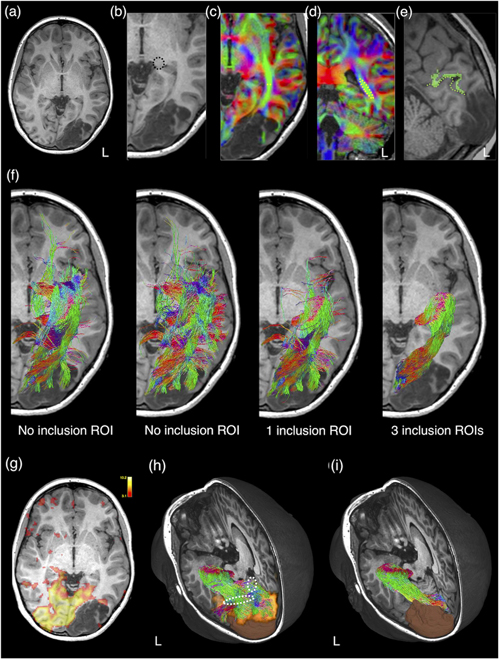

Targeted tractography utilises strategically placed ROIs typically based on a priori knowledge about the WM tract anatomy, to impose anatomical constraints for streamline propagation/tracking (see figure 8). They include: the seed ROI, which defines the starting point of streamline tracking; the inclusion ROI (also known as the 'AND' ROI or 'waypoints'), which defines the obligatory tract passage where the tract is known to pass through; and the exclusion ROI (also known as the 'NOT' ROI), which defines the region the tract is known not to pass through. Streamlines intersecting the exclusion ROI are rejected.

Figure 8. A schematic illustration demonstrating the regions-of-interest (ROIs) strategy used for targeted tractography. Here, we have four different coloured white matter tracts organised in complex fibre arrangements, including crossing, kissing, and overlapping patterns. To reconstruct the blue-coloured white matter tract, the tracking ROIs are placed based on a priori anatomical knowledge about all four white matter tracts. ROI-A and ROI-B can be used as either the seed ROI (representing the tracking starting point) or the inclusion ROI (representing the obligatory passage of this tract). ROI-C, ROI-D, and ROI-E are used as exclusion ROIs (representing regions where the blue-coloured tract is known not to pass). Note that without using the ROI-E as an exclusion ROI, false positive reconstruction can be produced (i.e. the solid black-coloured streamline) due to streamlines propagating over the crossing-fibre region between the blue- and green-coloured white matter tracts.

Download figure:

Standard image High-resolution imageThe streamline tracking in targeted tractography is also dependent on the spatial and angular resolution of DWI data (Vos et al 2016, Schilling et al 2017), and many algorithmic variables that can be subjectively selected by the tracking operator. These include the dMRI model (e.g. DTI versus high-order models, such as CSD), the tracking algorithm of choice (e.g. deterministic versus probabilistic); and a set of pre-defined tracking parameters, e.g. the retained streamline numbers, the maximum and minimum retained tracking lengths, the size and angle between successive per-voxel streamline steps, and the criteria defined for track termination (Jeurissen et al 2019). Thus, performing targeted tractography in neurosurgical settings requires delineation of tracking ROIs by operators with expert anatomical knowledge, experience in adapting the ROI strategies in the presence of pathology, and expertise with chosen tractography techniques and their related technical limitations.

5.1.1. Using anatomy-based ROIs

These are typically delineated manually based on the recognisable anatomical structures or regions (such as the cerebral peduncle for corticospinal tract reconstruction) or based on the WM regions delineated by the contrast related to the principal diffusion direction, as evident on the DEC map (Pajevic and Pierpaoli 1999, Calamante et al 2010). For example, the sagittal stratum, a deep WM region adjacent to the occipital ventricular trigone, is an obligatory passage for optic radiation, thus commonly adopted as the inclusion ROI for its tractography reconstruction (Yang et al 2019) (see also figure 9). The sagittal stratum can be identified and delineated on the DEC map as a green-colour region adjacent to the ventricular trigone, containing predominantly anterior-to-posterior oriented WM fibres (Yang et al 2019). In addition to manually defined ROI, further anatomical constraints to specific cortical and subcortical GM regions can be defined by using automated individual brain GM parcellation schemes derived from structural MRI or using warped atlas-based brain regions into the subject native imaging space. Targeted tractography based on manually placed or template-driven anatomical constraints can result in reconstructions that very accurately reflect the ground truth WM connections mapped by axonal neurotracer in sectioned macaque brain (Schilling et al 2020a). Increasing adding well-chosen ROIs, based on a priori anatomical knowledge about the WM tract, can further improve the anatomical precision of the tractography result (see figure 9).

Figure 9. The impact of different regions-of-interest (ROIs) strategies used in targeted tractography of the left optic radiation. This is a 13 year old girl with refractory visual focal epilepsy referable to a left occipital developmental brain tumour (dysembryoplastic neuroepithelial tumour; as shown on anatomical T1-weighted image in (a)). The optic radiation tractography can be reconstructed entirely using anatomy-based ROIs. The seed ROI is placed at the lateral geniculate body ((b); dashed black circle). An inclusion ROI is placed at the sagittal stratum, an occipital periventricular deep white matter region, containing anterior-posteriorly oriented optic radiation fibres, identified as a green coloured region on directional encoded colour maps (dashed yellow line and circle in respective axial (c) and coronal (d) planes). Note that blue colour encodes the superior–inferior orientation, and red colour encodes the left–right orientation. (e) Another inclusion ROI is placed at the pericalcarine cortex on either side of the left calcarine sulcus (dashed green line). Automated anatomical segmentation (in green) produces erroneous parcellation of the left pericalcarine cortex. The pericalcarine cortex is delineated manually in this instance. (f) The anatomical accuracy of the optic radiation tractography reconstruction improves with increased numbers of well-defined ROIs. All tractography results are shown in the same colours as those used for the directionally encoded colour maps. Here, we show the differences in the tracking results by using different numbers of inclusion ROIs. The same exclusion ROIs (not shown here) are used in all reconstructions. Note the far left panel in (f), a seed ROI is placed at the lateral geniculate body. In the next panel, a seed ROI is placed at the sagittal stratum. An alternative way for targeted tractography reconstruction is to use ROIs based on functional data. In this case, visual cortical activation derived from visual-task BOLD-fMRI (g) is used as an inclusion ROI. (h) A 3D rendered image of the resultant optic radiation tractography, the brain tumour segmentation (in brown) and the activated visual cortex (in orange). The tracking result should be interpreted with caution. Since direct geniculate-extrastriatal connections are rare in humans (Locke 1967, Ellis 2005, Clatworthy et al 2010), the portion of the tracking result may represent false positive reconstructions (dashed white outlines). (i) A 3D rendered image of the same optic radiation tractography using entirely anatomy-based ROIs, as described previously, is included here for comparison purpose. Material acronyms: L (left), ROI(s) (region-of-interest(s)).

Download figure:

Standard image High-resolution imageThe aforementioned ROI strategy will need to be modified if the brain anatomy is obscured by the presence of pathology or by the previous neurosurgical intervention (tracking in the post lesion resection regions, for example). While the decision is likely to be individualised, the general principle is to place ROIs only in areas with recognisable anatomy, and avoid placing precise ROIs in areas affected by pathology or surgery, which would introduce tracking bias due to ambiguous a priori anatomical knowledge. The presence of pathology may also render automated brain parcellation regions useless (see figure 9), or manual editing by expert raters is mandatory to ensure the delineated ROI satisfactorily encompasses the targeted anatomy (although the editing process may itself introduce further bias). This process, however, can be more time consuming than manually defining the ROI in the first instance.

5.1.2. Using functional-based ROIs

Another method is to use functional brain data to guide ROI definition, resulting in functionally more relevant targeted tractography reconstruction (Staempfli et al 2008, Tournier et al 2011) (see figure 5). This type of ROI strategy may be indicated when the delineated brain anatomy is obscured by the presence of pathology, and/or questions arise to visualise WM tract components subserving specific functions that may have reorganised topological functional representation (e.g. using finger-tapping BOLD-fMRI to help map out the finger-motor fibres of the corticospinal tract, for a brain tumour residing in the hand knob portion of the primary motor cortex). Examples of functional imaging modalities used to localise eloquent cortical regions include (but not limited to) the peak activation regions defined by task-based BOLD-fMRI (Smits et al 2007, Kleiser et al 2010, Sanvito et al 2020), nTMS (Frey et al 2012, Conti et al 2014, Krieg et al 2015, Picht et al 2016, Rosenstock et al 2017, Weiss Lucas et al 2017, Rosenstock et al 2020, Fekonja et al 2021), and MEG (Gaetz et al 2010). Similarly, functional brain mapping obtained through either cortical DES (Berman et al 2004) performed with electrophysiology monitoring (Maesawa et al 2010); or intracranial electrodes (i.e. the grid electrode used for intracranial electrocorticography in epilepsy surgery or electrodes used in deep brain stimulation surgery) can be used to define the tracking ROI.